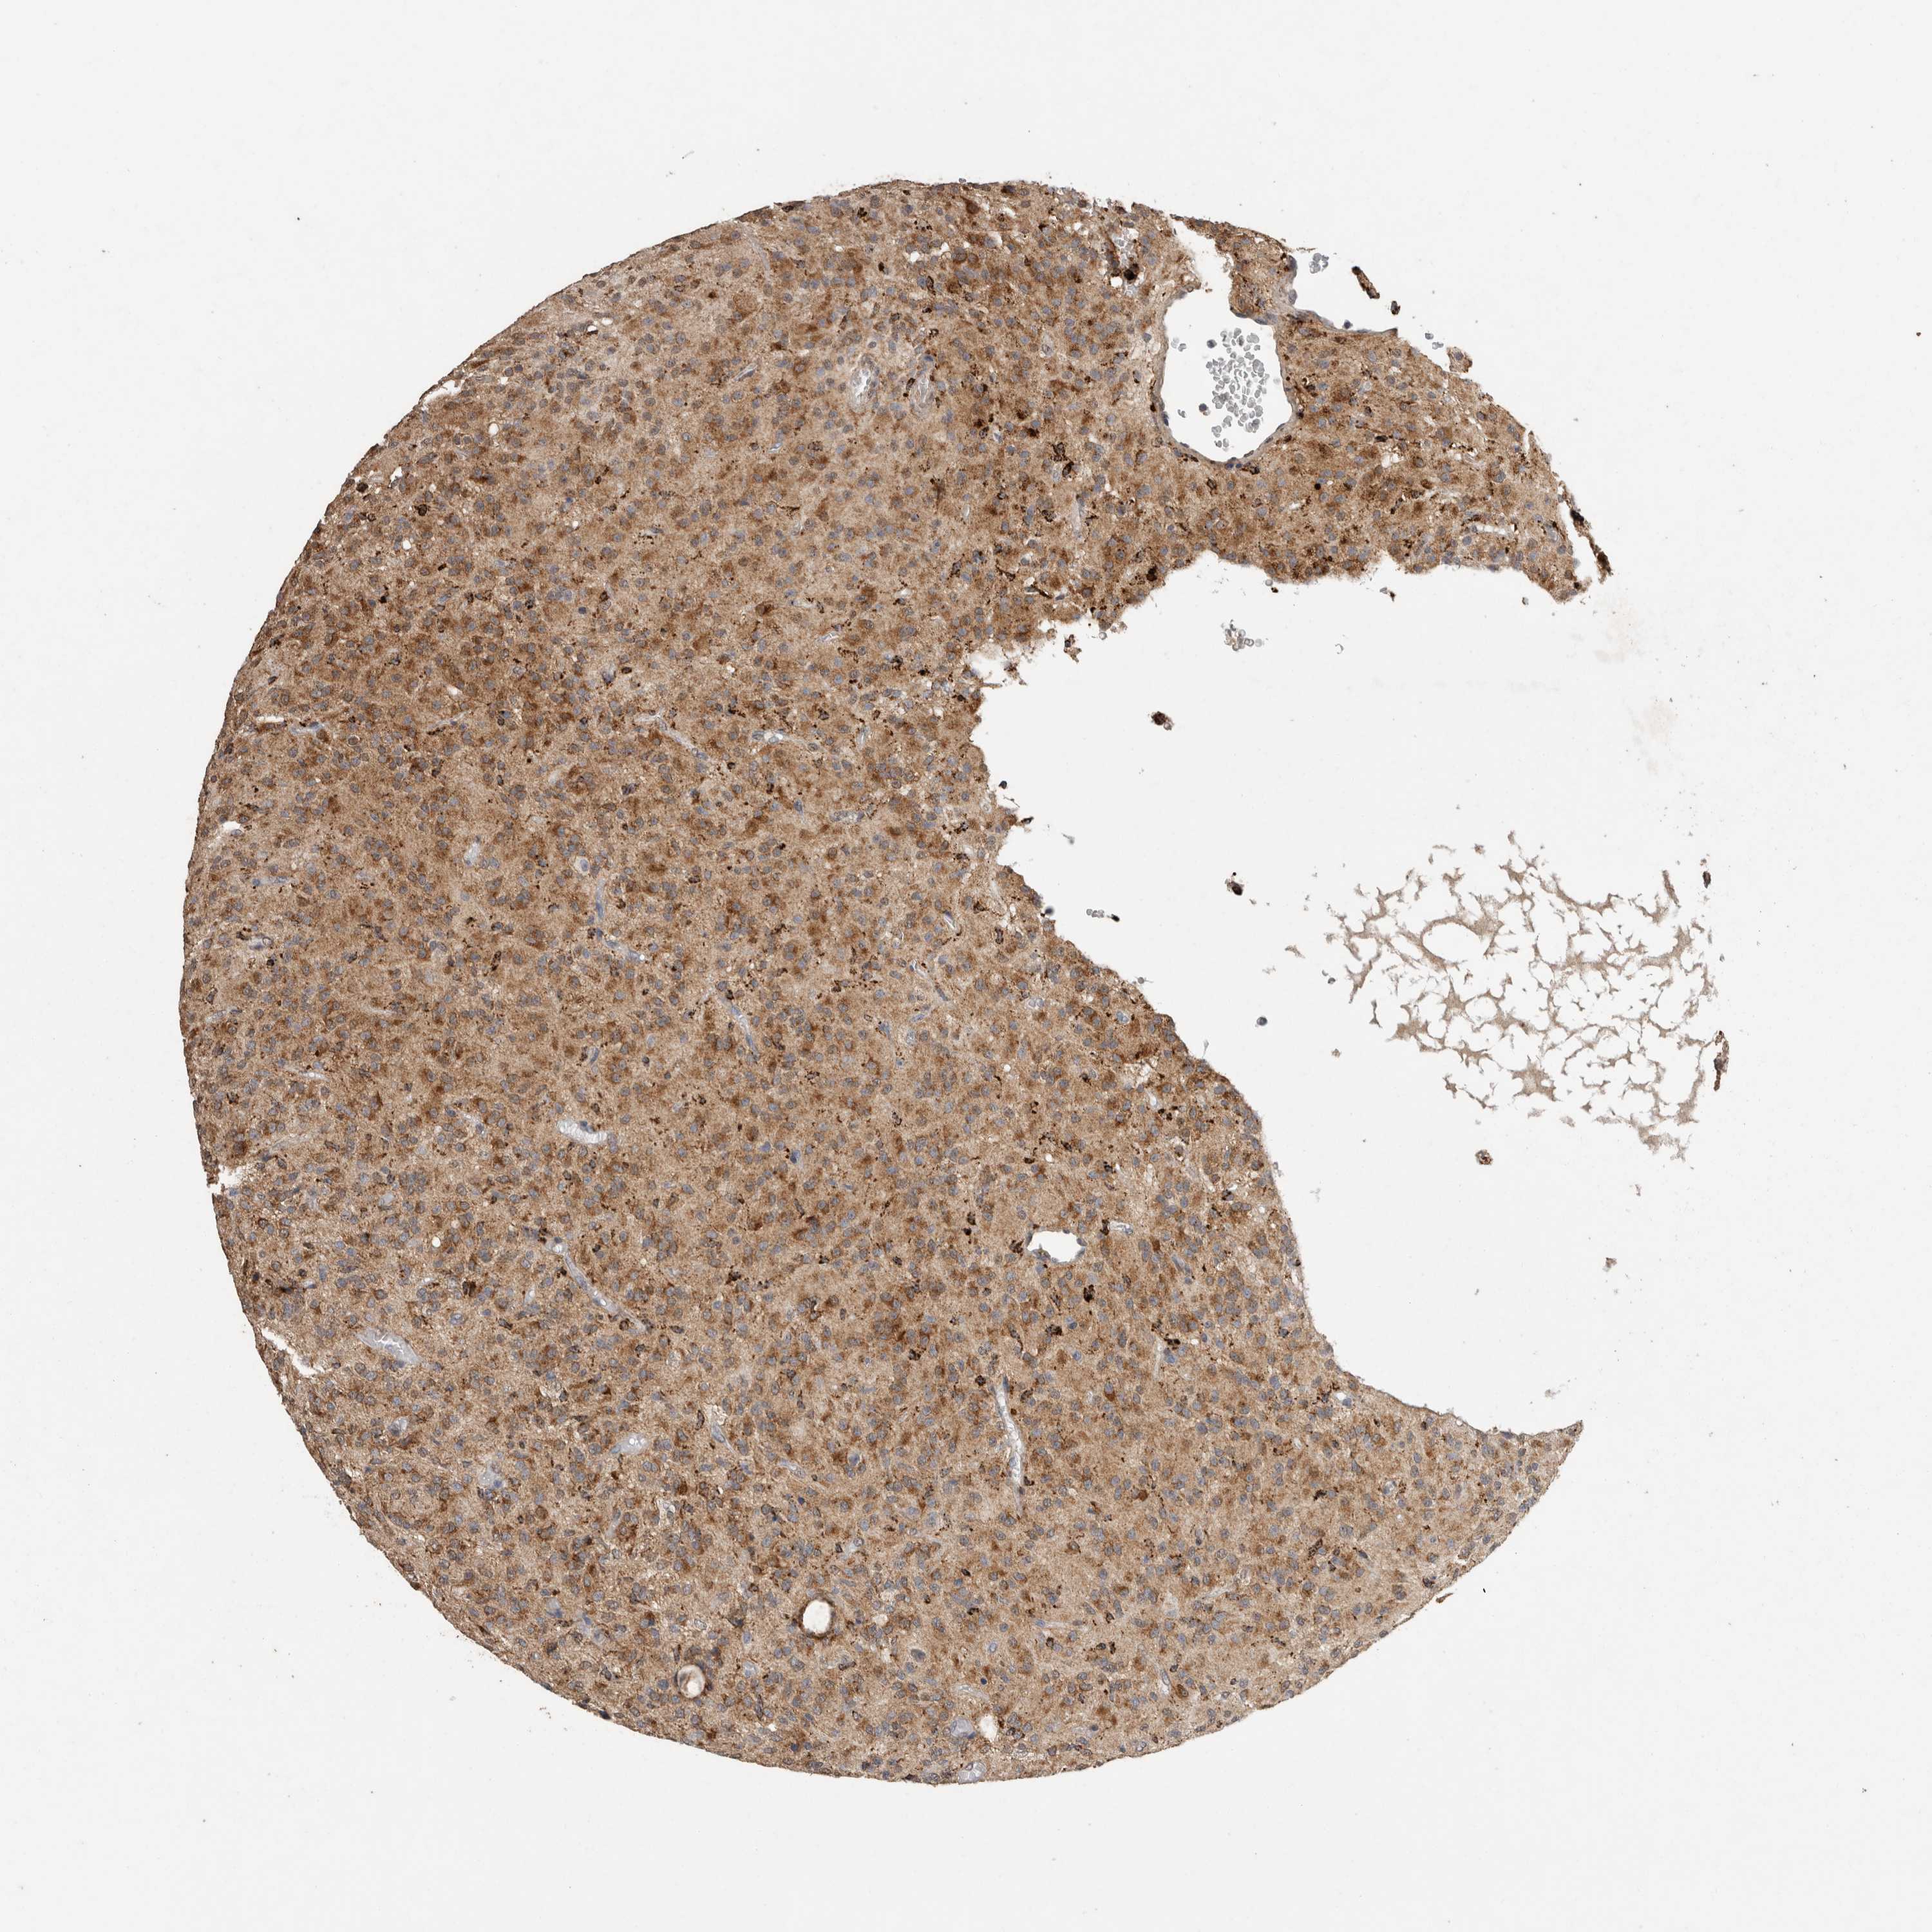

GLIOMA - Protein expressioni

A mouse-over function shows sample information and annotation data. Click on an image to view it in a full screen mode. Samples can be filtered based on level of antibody staining by selecting one or several of the following categories: high, medium, low and not detected. The assay and annotation is described here.

Note that samples used for immunohistochemistry by the Human Protein Atlas do not correspond to samples in the TCGA dataset.

Antibody stainingi

Antibody staining in the annotated cell types in the current human tissue is reported as not detected, low, medium, or high, based on conventional immunohistochemistry profiling in selected tissues. This score is based on the combination of the staining intensity and fraction of stained cells.

Each image is clickable and will lead to virtual microscopy that enables deeper exploration of all samples and also displays staining intensity scores, fraction scores and subcellular localization as well as patient and tissue information for each sample.

Antibody HPA038604

Antibody CAB025607

Staining

High

Medium

Low

Not detected

Intensity

Strong

Moderate

Weak

Negative

Quantity

>75%

75%-25%

<25%

None

Location

Nuclear

Cytoplasmic/membranous

Cytoplasmic/membranous,nuclear

Glioma, malignant, High grade

Glioma, malignant, Low grade